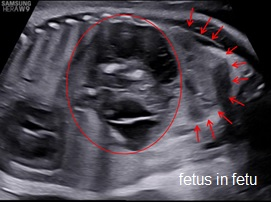

Fetus in Fetu (FIF) là bất thường rất hiếm gặp của song thai một trứng, trong đó một thai không trưởng thành sống ký sinh trong cơ thể của thai bình thường

Xem thêm